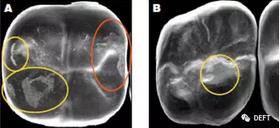

有學(xué)者的研究證實(shí):釉面會(huì)被迅速磨耗而且變得粗糙,反而會(huì)磨耗對(duì)頜牙。(圖3)

圖3  A圖:顯示了對(duì)頜牙在BruxZir全鋯冠上造成的磨損的平面,黃色圓圈代表復(fù)合樹(shù)脂和釉質(zhì),橙色圓圈代表瓷。B圖:顯示了對(duì)頜牙為鑄造金屬修復(fù)體時(shí),對(duì)切削類(lèi)e.maxCAD單冠造成的磨損平面。兩種牙冠表面都有小的磨損平面,而且他們的對(duì)頜牙都顯示出了良好的結(jié)果。臨床上,對(duì)頜牙的每種材料(瓷、樹(shù)脂、釉質(zhì)、鑄造金屬)被磨損的程度幾乎是等同的。